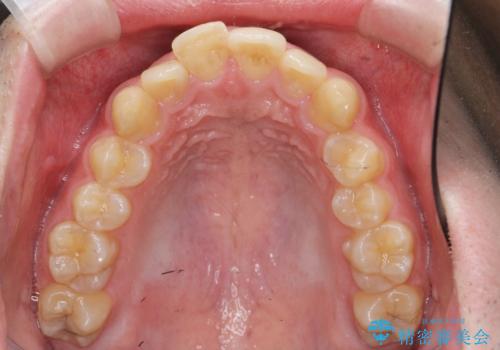

ガタつきの大きい前歯 インビザラインによるマウスピース矯正治療

- ガタつきの目立つ前歯の改善を求めて来院されました。

上顎前突、がたつきを改善すべく上顎臼歯の後方移動・ディスキングを行い歯並びの改善を計画します。

食事・歯ブラシ時以外の時間にしっかりとマウスピースを装着していただけたのでガタつきは大きく改善し良好な歯並びを得ることができました。